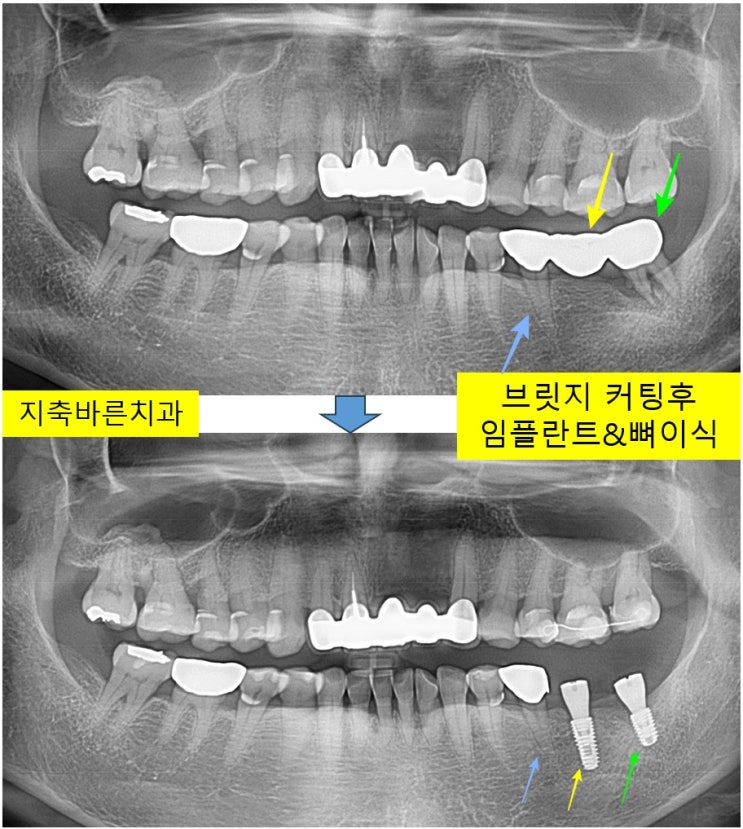

<브릿지 커팅 후 임플란트, 와이어 스플린트>지축치과 지축역치과 삼송치과 원흥치과 원당치과 구파발치과 파주치과 운정치과 화정치과 마두치과 일산치과 일산임플란트 파주임플란트 종로치과

열흘정도 전부터 왼쪽 아래부분 어금니가 씹을때 불편하시다며 2024년 5월 60대 Kㅁㅁ 님께서 내원해주셨...